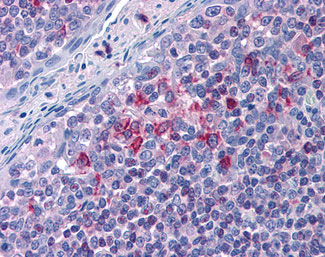

Anti-ALOX5AP / FLAP antibody IHC of human lung.

Anti-ALOX5AP / FLAP antibody IHC of human tonsil. |